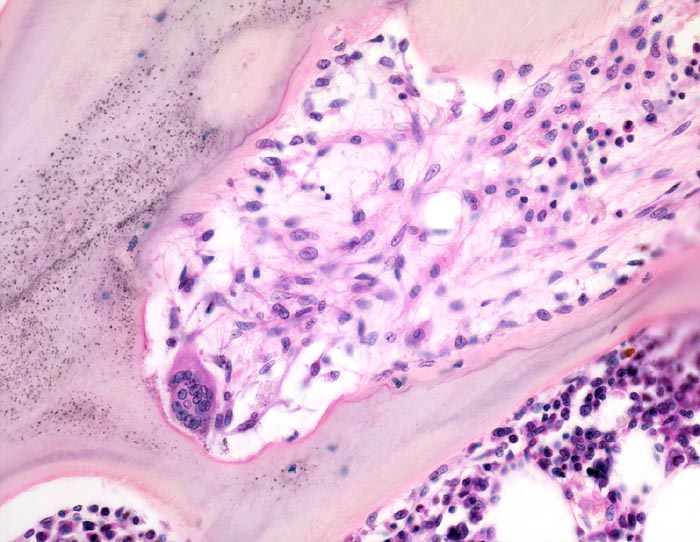

Histologisch findet sich beim Hyperparathyreoidismus eine gesteigerte Osteoklastentätigkeit mit Tunnellierung der Knochenbälkchen und gleichzeitig eine gesteigerte Knochenneubildung mit Fibrose der peritrabekulären Markräume. Die Maximalvariante eines sogenannten „Braunen Tumors“ -Osteodystrophia fibrosa generalisata cystica von Recklinghausen- kommt heute in Mitteleuropa praktisch nicht mehr vor. Die braune Farbe dieses Tumors wird durch sekundäre Einblutungen und Siderinablagerungen verursacht.

• Dünne Spongiosabälkchen mit herdförmiger peritrabekulärer Fibrose.

• Vermehrte Osteoklastentätigkeit: Spongiosabälkchen mit tiefen Resorptionslakunen, welche die Bälkchen z.T. tunnelartig aushöhlen.

• Die Resorptionslakune ist aufgefüllt mit lockerem Bindegewebe gebildet von Fibroblasten.